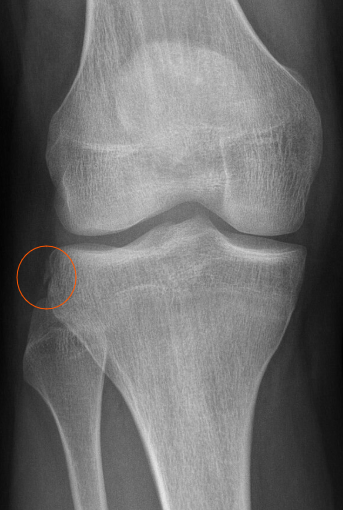

단순 방사선 검사(X-ray)는 골절 여부 확인에 사용되며 인대 파열 직접 확인에는 한계가 있음.

※Segond fracture는 외측 경골과 상부 외측 경골 플래토(lateral tibial plateau)의 작은 관절면에서 발생하는 견열 골절(avulsion fracture)이며, 무릎 외측에 위치한 인대와 관절낭의 부착부가 분리되는 형태입니다.

Segond fracture와 ACL 파열(rupture)의 연관성

Segond fracture는 거의 75~100%의 경우에서 ACL 파열과 동반되어 나타나며, ACL 손상의 특징적인 방사선학적 징후(pathognomonic sign)로 간주됩니다.